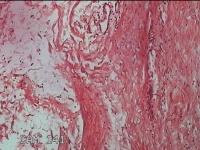

后颈部包块

性别

女

年龄

35岁

临床诊断

颈部皮脂腺囊肿

一般病史

发现后颈部包块半年余,伴近期局部隐痛不适,无发热。

标本名称

大体所见

灰白暗红色包块2x1.8x0.8cm一个,表面糜烂,包块表面有少许毛发,切面灰白粉红色,质中。